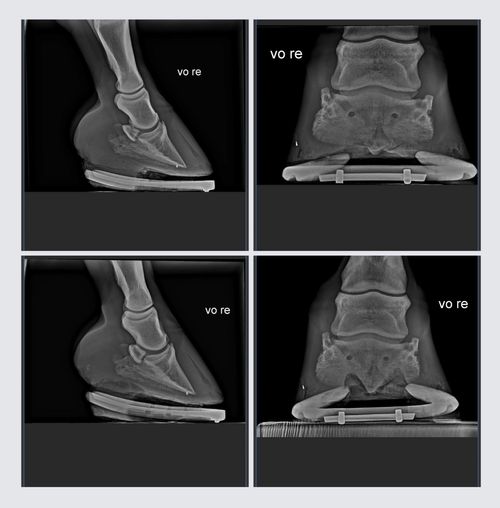

Ein fachgerechter Hufbeschlag ist für die Gesundheit und Leistungsfähigkeit Ihres Pferdes von entscheidender Bedeutung. Verwendet werden hierbei, qualitativ hochwertige Materialien und modernste Techniken, um die Hufe Ihres Pferdes zu schützen, die natürliche Bewegung zu unterstützen und potenziellen Beschwerden vorzubeugen.

Ein Hufschmied mit umfangreichen Erfahrungen und fundierten Fachkenntnissen im Bereich Hufbeschlag ist in der Lage, für jedes Pferd die passende Lösung zu finden und auch in komplexen Fällen sachgerechte Behandlungen durchzuführen. In dieser Rolle sind diese Fähigkeiten und das Wissen entscheidend, um den Bedürfnissen jedes Pferdes gerecht zu werden.

Eine effektive Zusammenarbeit an ihrem Pferd zwischen Tierärzten und Hufschmieden ist essenziell für die Förderung der Gesundheit und Leistungsfähigkeit. Durch einen regelmäßigen Austausch und die Erstellung gemeinsamer Behandlungspläne können potenzielle Probleme frühzeitig erkannt, Verletzungen vorgebeugt und Heilungsprozesse unterstützt werden.